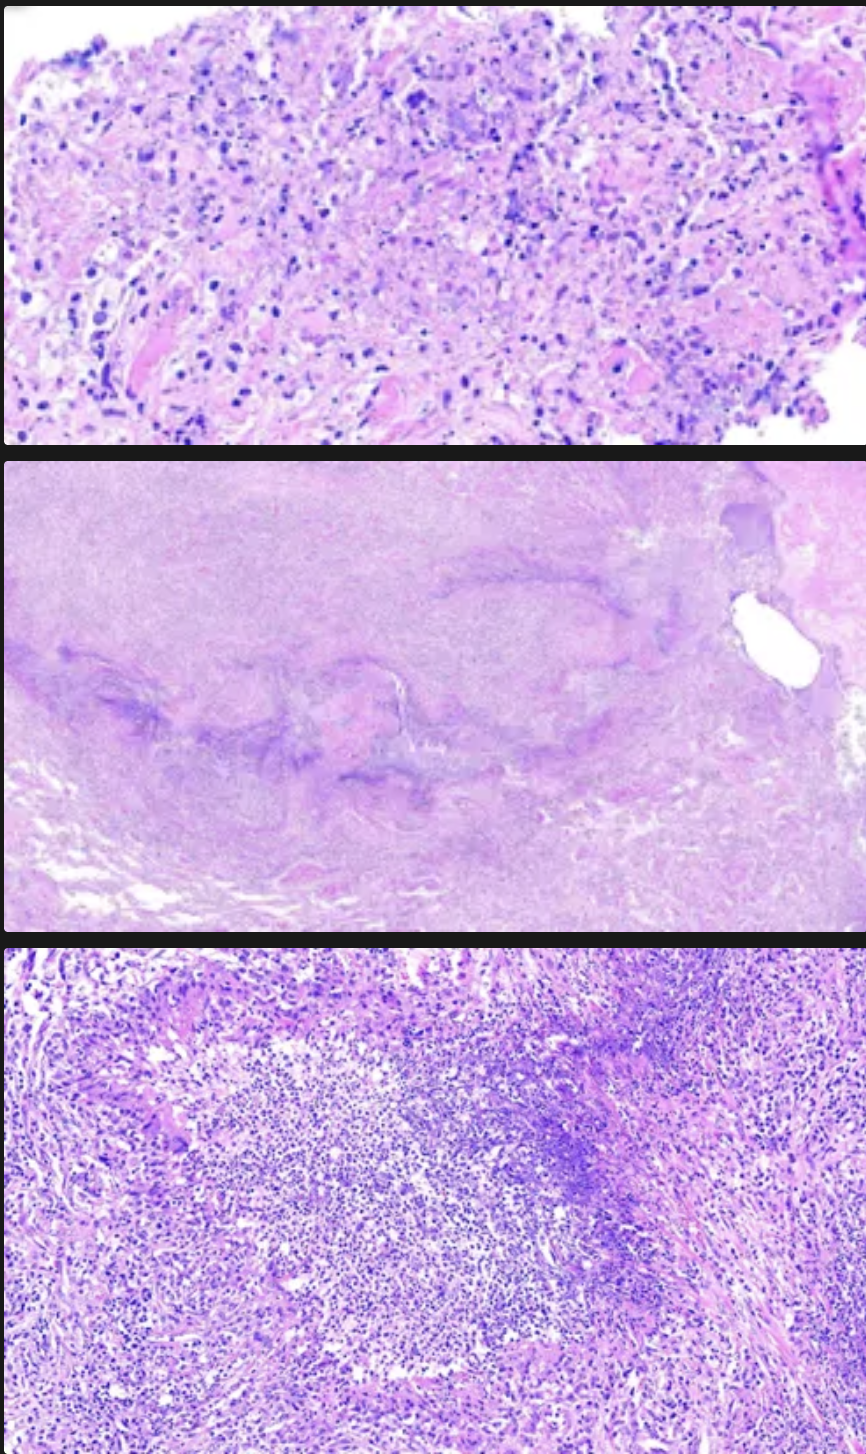

La granulomatosis con poliangitis (de Wegener), tiene granulomas con patrones _____ de necrosis central caseosa y estos granulos mas están rodeados por una zona de _______ con células gigantes e infiltrado leucocitario

Geográficos (contornos irregulares de la necrosis); Fibroblastos porliferativos

Cómo se ven los glomérulos en la glomerulonefritis infecciosa?

Glomérulos hipercelulares de gran tamaño

Infiltración de leucocitos (es global y difuso osea en tdoso los lóbulos de todos los glomérulos)

Proliferación de células endoteliales y mesangiales

Formación de semilunas

En la inmunofluorescencia de la glomerulopatia infecciosa, que depósitos célulares se pueden ver?

IgG

C3

C4

C5 - C9

Si la glomerulonefritis rápidamente progresiva es la tipo 2, cómo se verá en inmunofluorescencia?

Granular

En la microscopía electrónica que es lo que más hace que se distinga de la glomerulopatia infecciosa?

Depósitos definidos, amorfos y electrodensos en la vertiente epitelial de la membrana a modo de JOROBAS